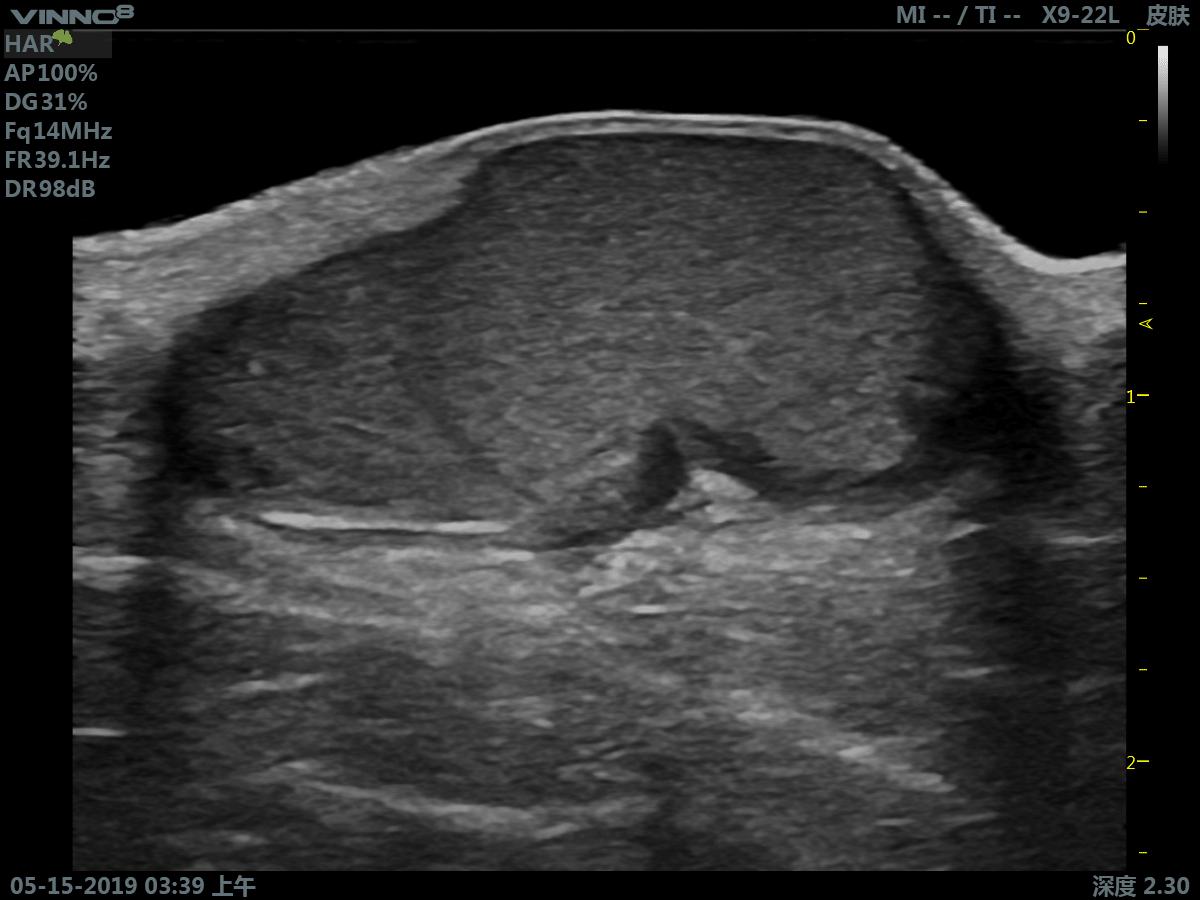

Портативный ультразвуковой сканер VINNO 8

Преимущества портативного УЗИ аппарата VINNO 8

- инновационная платформа RF обеспечивает суперчистое изображение в результате сверхвысокой скорости обработки данных

- сверхвысокая частота (до 23 МГц на линейном датчике)

Клиническое применение:

- мелкие объекты (включая щитовидную железу, молочную железу, семенники и т.д.)

3. Режим тканевой гармоники - технология выделения гармонической составляющей колебаний внутренних органов, вызванных прохождением сквозь тело базового ультразвукового импульса.